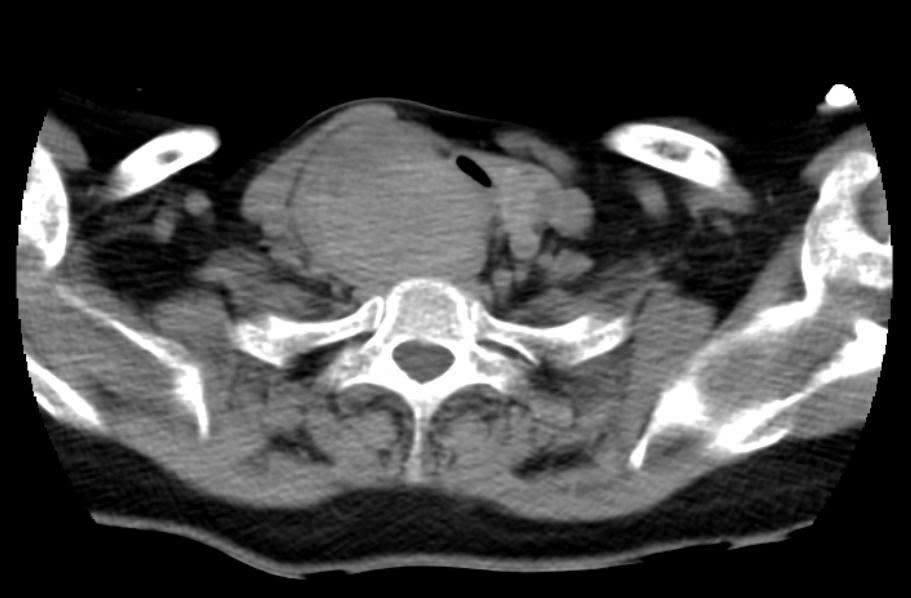

Các kết quả chụp cắt lớp cho thấy khối u chèn ép nghiêm trọng lên khí quản và thực quản, khiến đường thở chỉ còn khoảng hẹp nhất 2mm trên đoạn dài 20mm kéo dài từ góc hàm bên phải tới trung thất trên gây biến dạng giải phẫu. Đáng chú ý, khí quản của bệnh nhân bị đẩy lệch trái 2 cm, xẹp, dễ co thắt, khiến việc tiếp cận và bóc tách gặp nhiều rủi ro. Khối u tăng sinh mạch rất mạnh, nguy cơ chảy máu trong và sau phẫu thuật cao.

Ca mổ kéo dài hơn 3 tiếng, ekip phẫu thuật phải "đi ngược dòng", lần theo cấu trúc giải phẫu đã biến dạng để tiếp cận khối u. Trong quá trình mổ, các bác sĩ đã kiểm soát mạch máu, cầm máu triệt để, bóc tách tỉ mỉ để lấy trọn khối u mà không làm tổn thương thực quản, khí quản, thanh quản và đặc biệt không phải mở khí quản - điều thường xảy ra ở các ca khó tương tự. Trong mổ kiểm tra đoạn khí quản bị u thùy phải tuyến giáp chè ép xẹp, mềm, dài 2 cm.